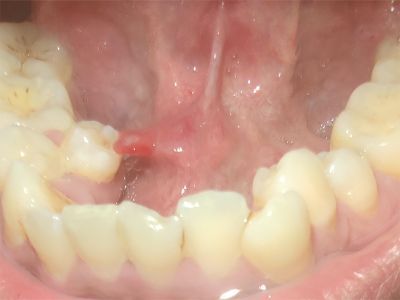

舌下腺囊肿口腔舌系带处有肿起的圆疙瘩图

舌下腺囊肿患者皮损为舌系带处透明带点红色的圆疙瘩样囊肿,局部触之有波动感,质地柔软而有弹性,但囊肿变大后可影响进食与发音。